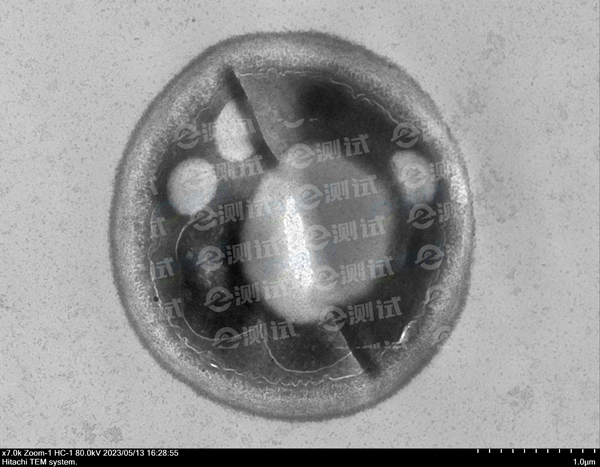

白色念珠球菌做TEM項(xiàng)目,拍到的照片中顯示菌體中央有一折線,這是什么原因造成的?

真菌細(xì)胞壁較厚,滲透難度大。

改善方法:固定液更換,具體配方:4%多聚甲醛+5%戊二醛: 溶解2g多聚甲醛于25 ml雙蒸水中,80°C水浴,搖動使之溶化后加1-3滴1M NaOH,使溶液澄清。冷卻后加10 ml25%戊二醛,再加15 ml 0.2PB,調(diào)pH備用,再加入Triton X-100(終濃度3% )。 此固定液中含多聚甲醛4%,戊二醛5%,屬高滲液,但固定效果不錯,尤其對細(xì)胞內(nèi)的微管保存較好。